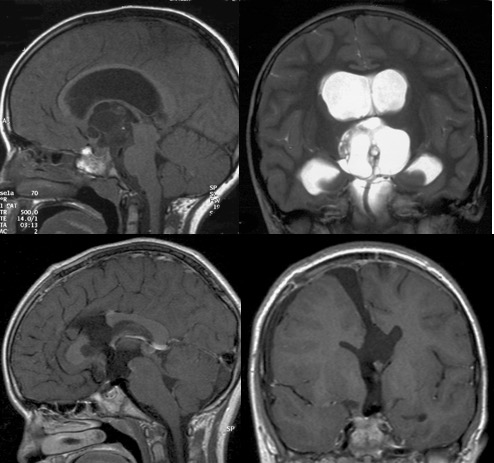

la voie trans-ventriculaire

il s’agit d’une voie transcalleuse étendue à la région suprasellaire. c’est don ici également une voie d’abord médiane.

elle est utile en cas de tumeur à développement intra-ventriculaire prédominant, en particulier les tératomes supra-sellaires. c’est une voie utile en urgence devant une hydrocéphalie tumorale aiguë, s’il n’est pas possible de faire une fenestration endoscopique. c’est également la voie d’abord pour les hamartomes hypothalamiques.

à noter qu’à la différence des craniopharyngiomes qui se séparent bien du tronc basilaire (du moins lors d’une première intervention), les tératomes peuvent adhérer intimement au tronc basilaire.

avantages

c’est une voie d’abord moins invasive et plus rapide que la voie sous-frontale. elle est mieux adaptée aux tumeurs avec extension intraventriculaire. elle peut être étendue en arrière par le soulèvement de la toile choroïdienne (voie inter-thalamo-trigonale)

inconvénients

elle nécessite l’existence d’une hydrocéphalie sinon les ventricules sont vraiment très petits. elle est également rendue difficile par la distance de travail nécessitant une instrumentation longue.

la voie trans-ventriculaire est limitée en avant par les piliers du trigone et la commissure blanche antérieure. par ailleurs, l’accès au tronc basilaire est très étroit et distal par cette voie.